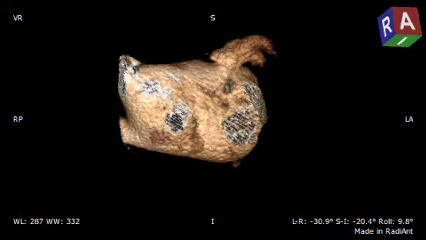

术前CTA确认心耳形态及位置

低位双分叶型左心耳

术前检查:心脏CT三维重建确认开口直径与心耳深度

RAO30度

CAU20度

左心耳大小20.1*17mm

RAO0度

CRA20度

左心耳大小20.3*15.5mm

RAO170度

CAU30度

左心耳大小20.2*17mm

CT三维平面左心耳开口形态及大小

左心耳开口近圆形,MPR周长66.4mm,化圆直径21.1mm,预选LAFDQ-23封堵器进行封堵